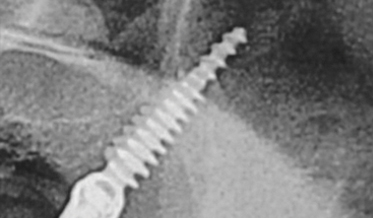

Using Three Familiar Radiographic Shapes to Improve Dental Implant Longevity